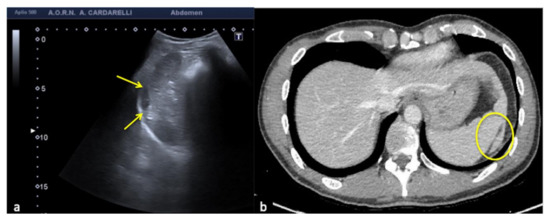

Figure 16. Coronal US scan of the left hypochondrium (a) shows a crescent-shaped hypoechoic area misinterpreted as hematoma (arrows) between the surface of the spleen and the left hemidiaphragm in a 25−year-old man investigated for trauma. On CT scan (b) it appears to be a hypertrophy of the left hepatic lobe with splenic kissing (circle).